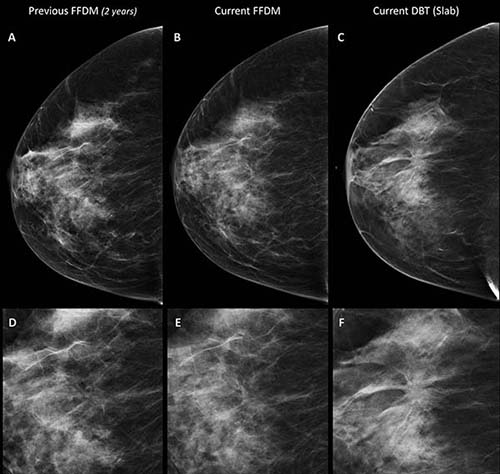

A combination of digital mammography and tomosynthesis detects 90 percent more breast cancers than digital mammography alone, according to a new study in Radiology.

To learn more about the impact of digital breast tomosynthesis (DBT) on sensitivity and recall rate, researchers compared results between 9,777 women randomized to undergo digital mammography and DBT and 9,783 randomized to have digital mammography alone.

The combination of digital mammography and DBT detected 8.6 cancers per 1,000 cases, a rate almost twice that of the 4.5 per 1,000 detected by mammography alone. The recall rate was 3.5 percent in both groups. DBT alone detected 72 of 80 cancers found in the DBT and digital mammography group.